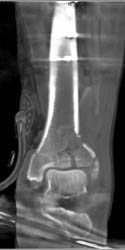

Tibial Fracture and Open Wound